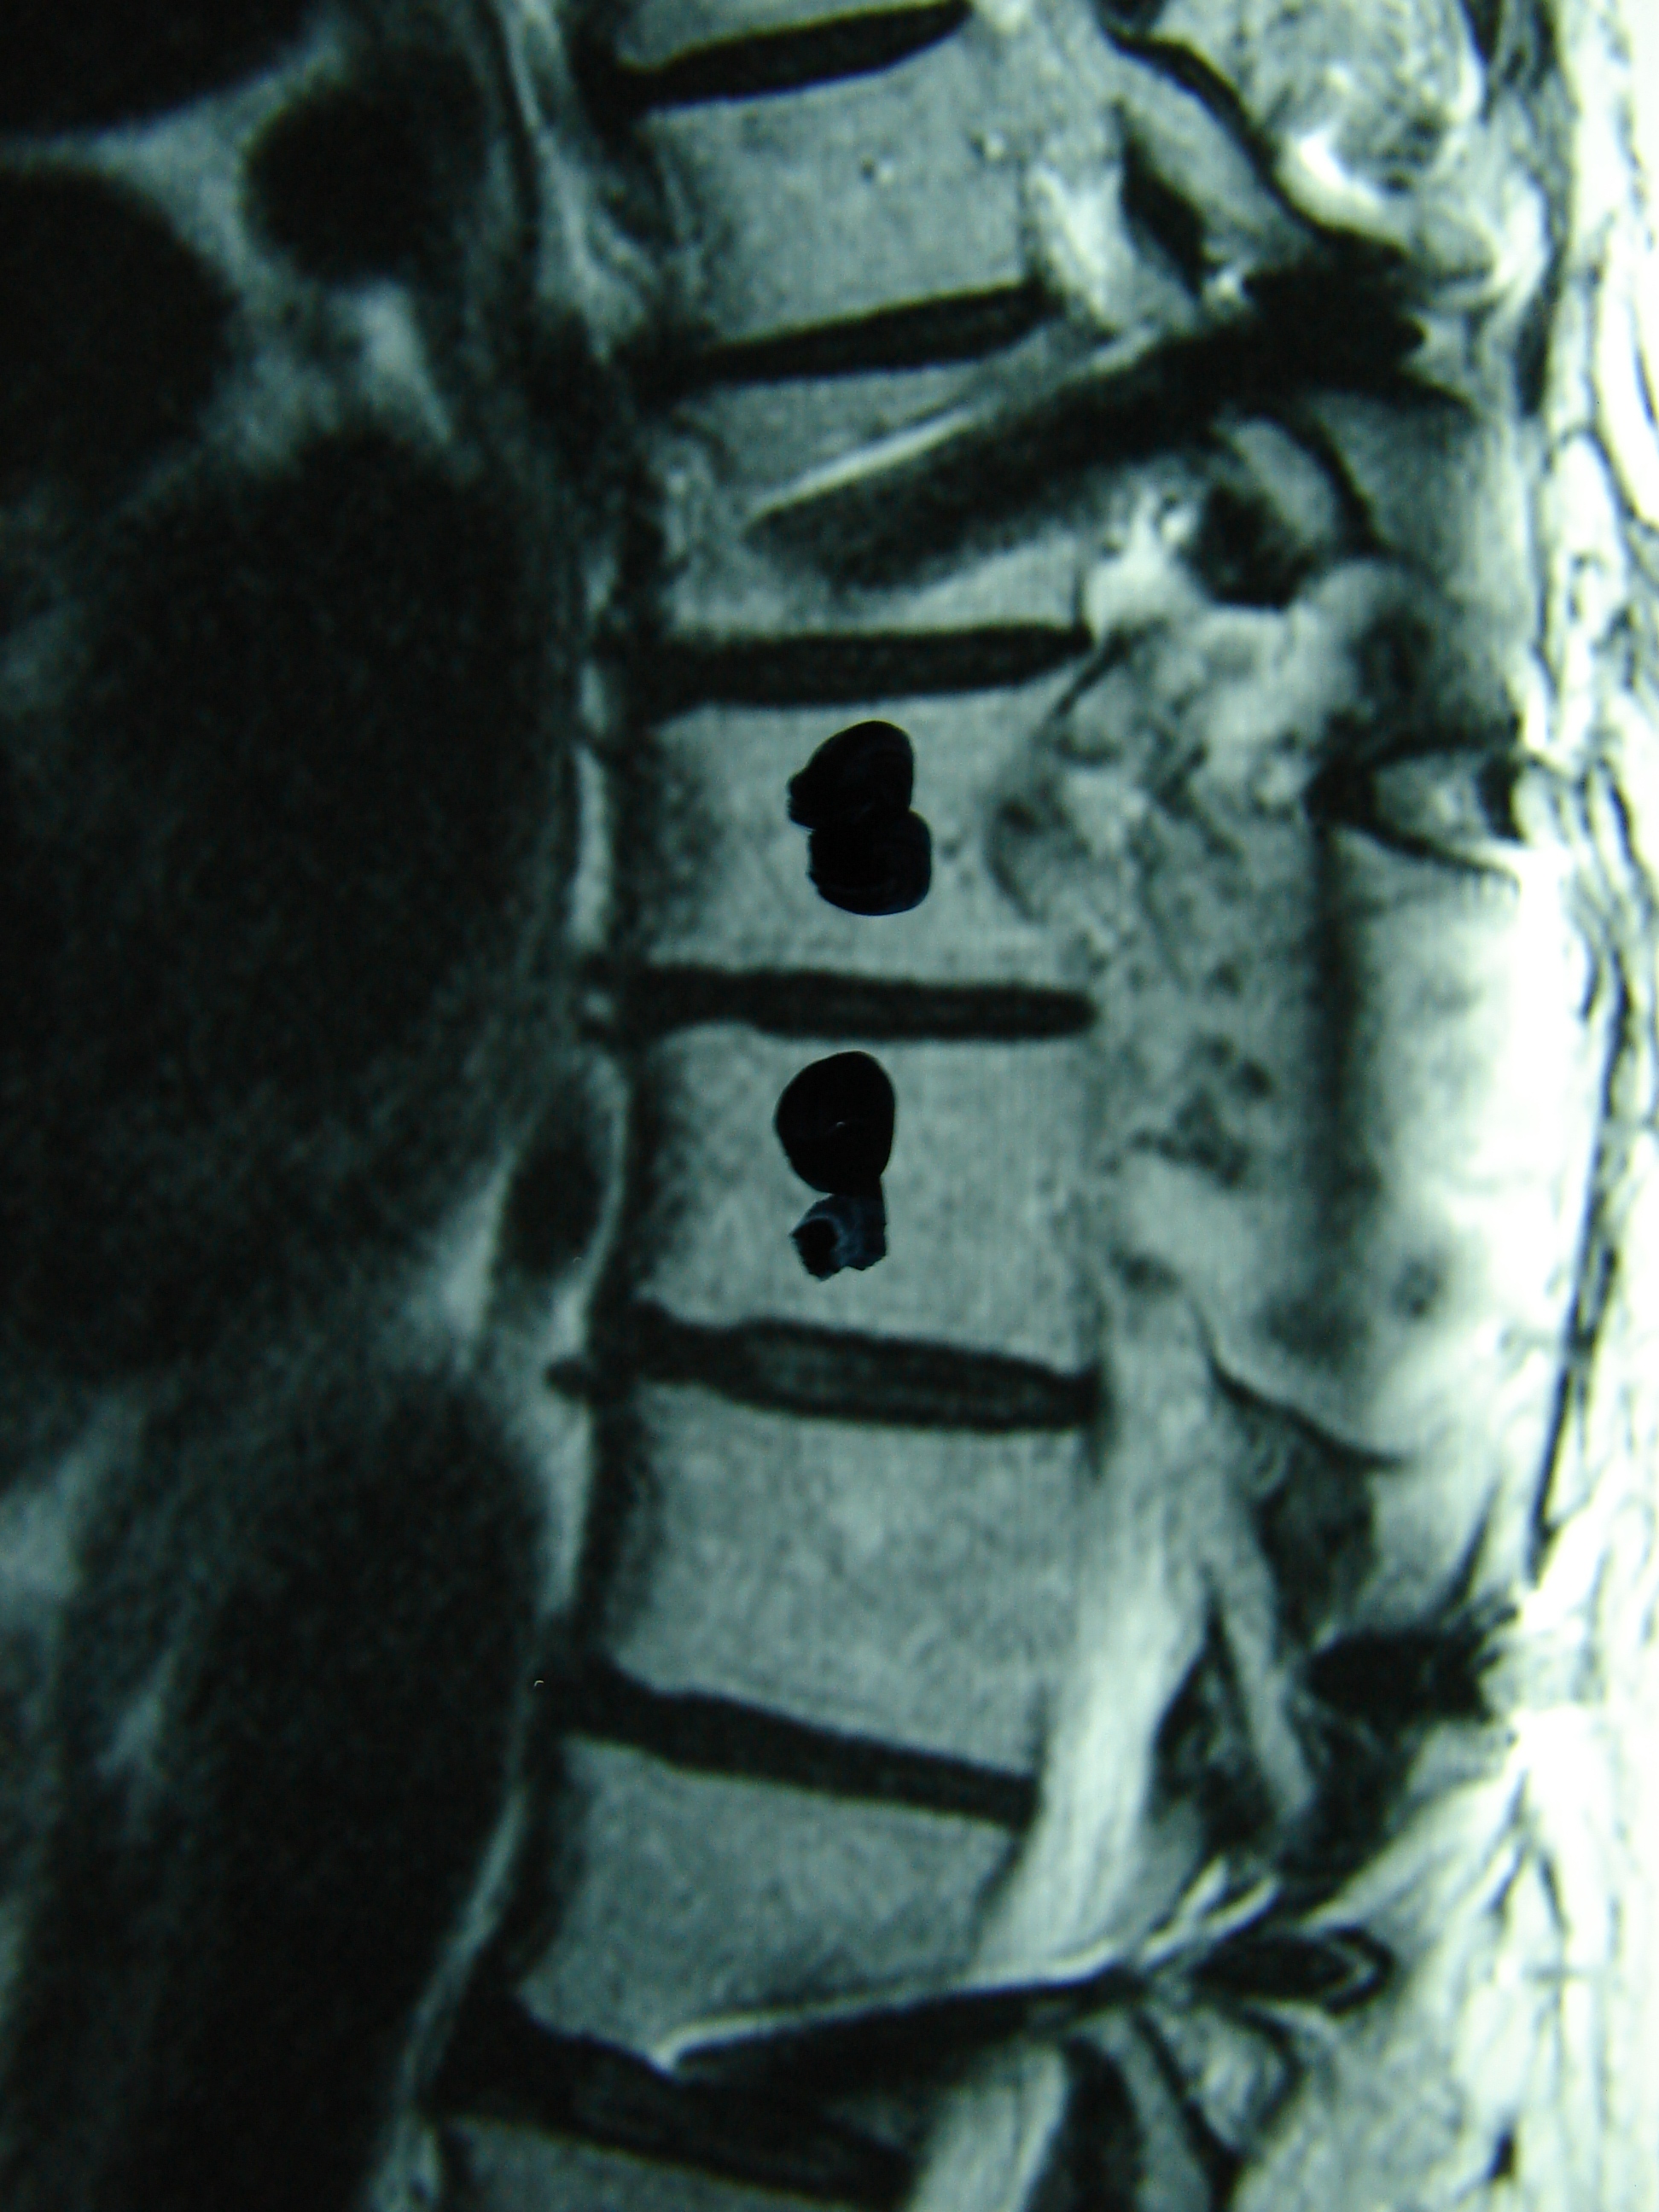

Εικόνα 2 α,β,γ,δ,ε,ζ

Μαγνητική Τομογραφία – Οβελιαία λήψη- Τ2 και Τ1

Παρατηρείται η ύπαρξη κακοηθούς μάζας επεκτεινόμενης εντός του σπονδυλικού σωλήνα.